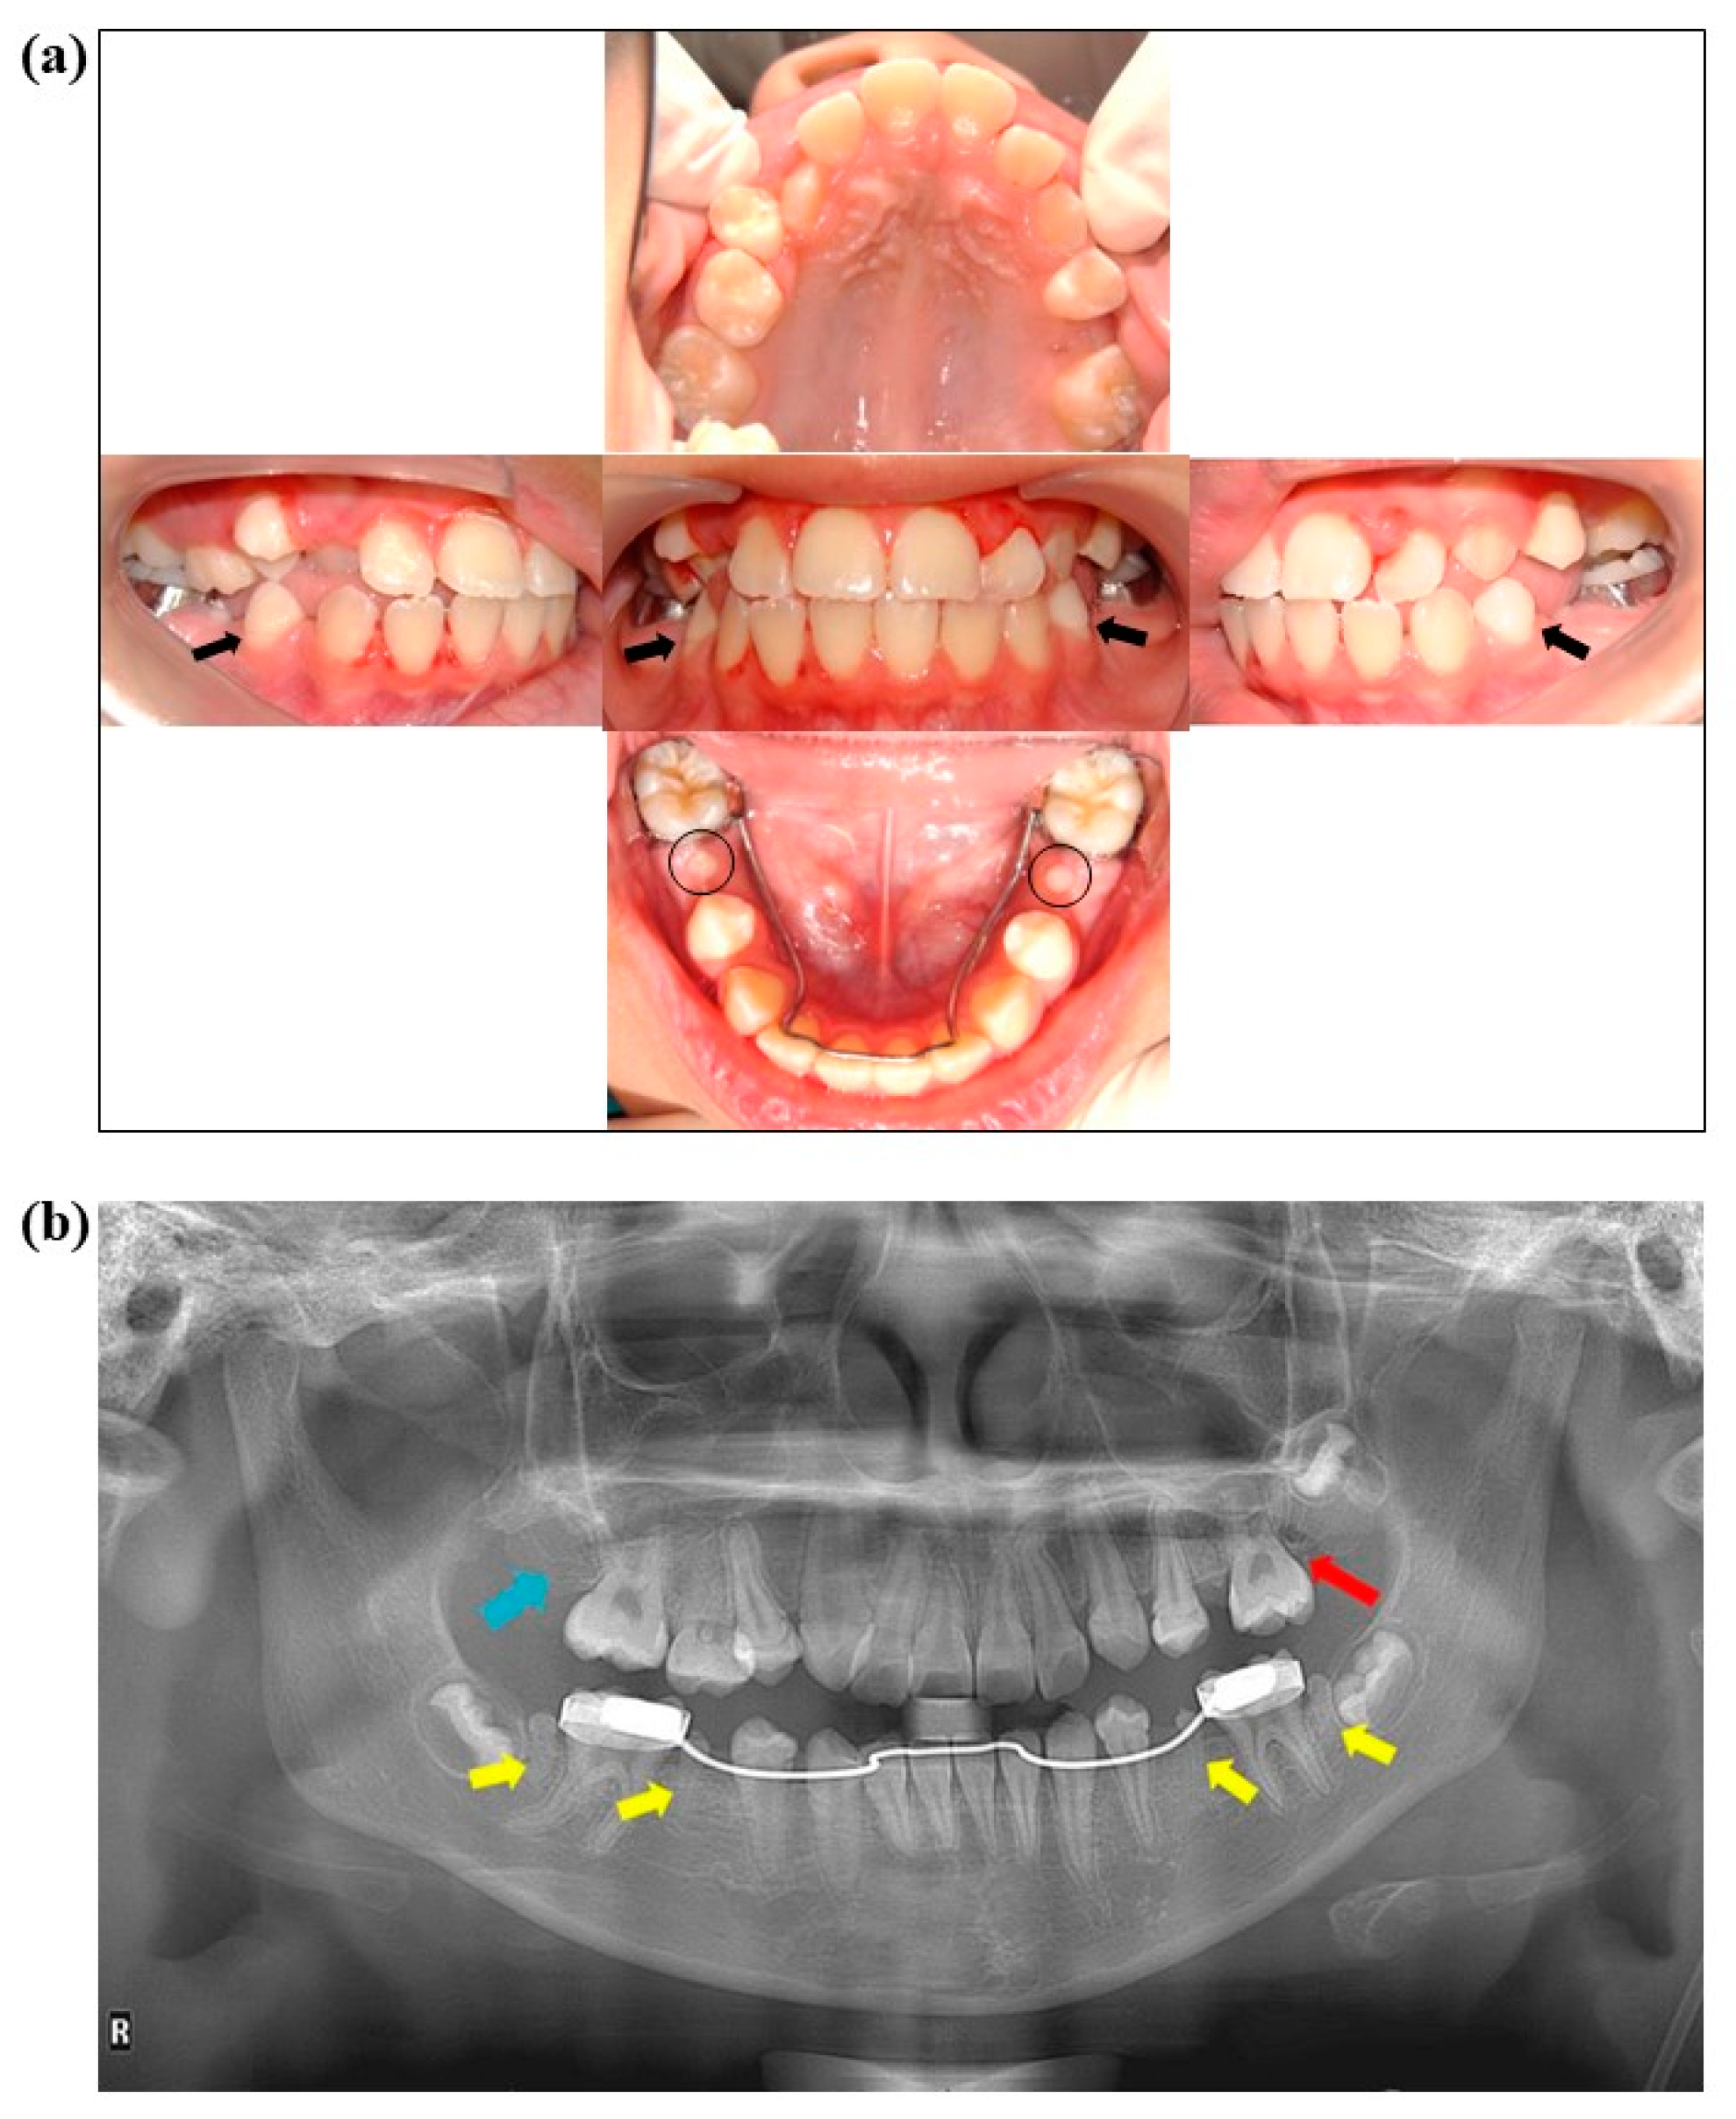

2. Case Presentation